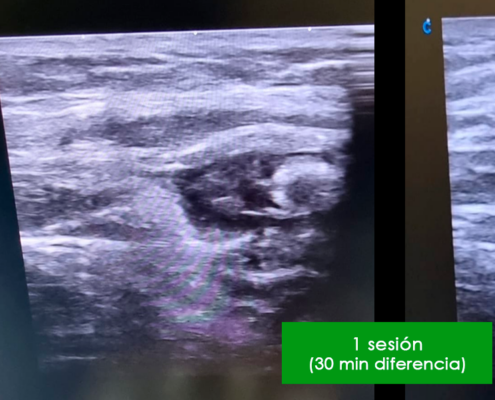

Los mecanismos de acción generados por la diamagnetoterapia se resumen en:

- Bioestimulación endógena

- Control del dolor

- Vehiculización transdérmica de medicamentos

- Movimiento de líquidos